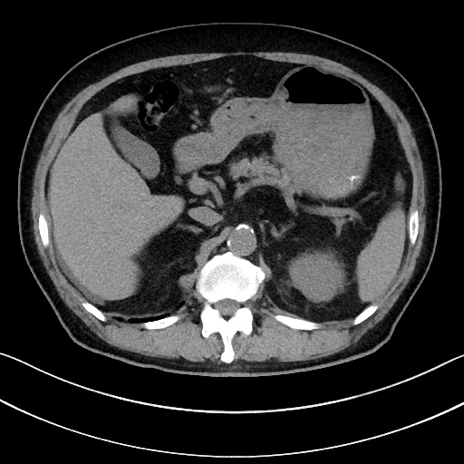

症例15(横断像)

【症例】70歳代男性

【主訴】腹痛

【現病歴】今朝から腹痛あり。全体的に痛い。特に左上の方。排ガスが今日はない。冷や汗が出る。

【既往歴】直腸癌術後

【身体所見】左側腹部〜上腹部に圧痛あり。腹膜刺激症状明らかなではない。軽度反跳痛。左下腹部に術後瘢痕あり。

【データ】WBC 7700、CRP 0.02